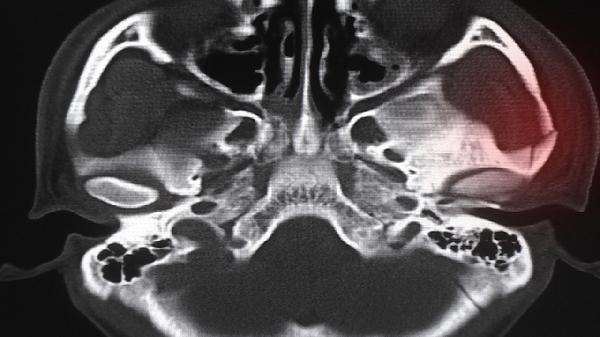

如果骨龄明显偏大伴随生长发育异常,建议咨询儿科或内分泌科医生。可能需要进行激素水平检测、骨龄评估及影像学检查,排除性早熟、甲状腺功能异常等潜在疾病。医生可能会开具促性腺激素释放激素类似物如醋酸亮丙瑞林注射液等,用于抑制青春期进展。